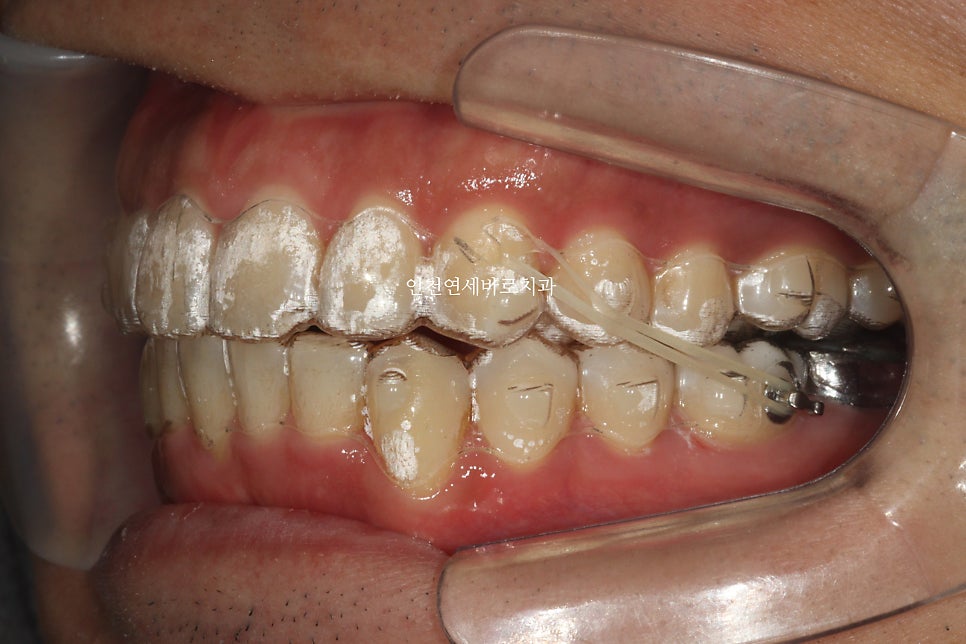

한번의 재제작을 시행하였습니다.

치료 전과 후의 비교입니다.

교합도 양호하게 마무리.

과개교합의 치료를 인비절라인으로 할때는 중요한 포인트가 몇개 있습니다.

이걸 챙기지 않으면 치료가 엄청 길어질 수 있습니다.

악궁의 확장을 통한 앞니의 후방이동도 최대한 이루어냈습니다.